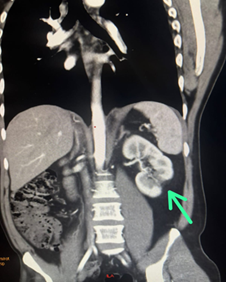

Se realizó angiotomografía de aorta total, tórax, abdomen y pelvis donde se llegó al diagnóstico de tromboembolismo pulmonar (TEP) agudo izquierdo, trombosis parcial de la vena renal izquierda (figura 5A) y signos de infarto renal bilateral (figura 5B).

Figura 5. Angiotomografía de aorta, tórax, abdomen y pelvis. A. La flecha muestra el déficit de relleno en la vena renal izquierda. B. La flecha indica el área de infarto renal izquierdo.